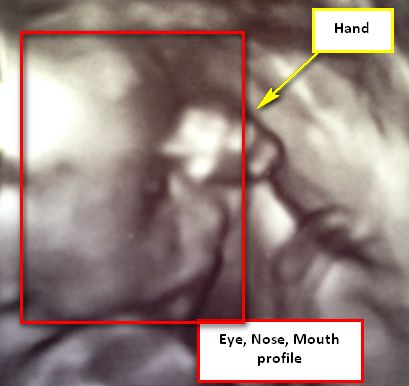

I was able to get 3D pics at both the sex check elective ultrasound we had at 15 weeks and at our anatomy scan at 19 weeks. This is his 19 week pic. I will be having at least one more ultrasound around 28 weeks to check on growth because I have ulcerative colitis and she will likely show us some 3D pics then as well.